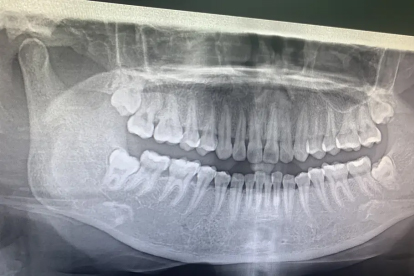

智齿冠周炎急性发作期牙龈红肿明显,伴随局部化脓或张口受限时,直接拔牙可能加重感染扩散。此时需通过生理盐水冲洗盲袋,配合使用甲硝唑片、阿莫西林胶囊等药物控制感染。炎症控制后1-2周,口腔医生会通过曲面断层片评估智齿位置,若存在阻生、龋坏或压迫邻牙等情况,可安排微创拔牙手术。采用超声骨刀分牙拔除能减少骨组织损伤,术后配合冷敷和头孢克肟颗粒预防感染。